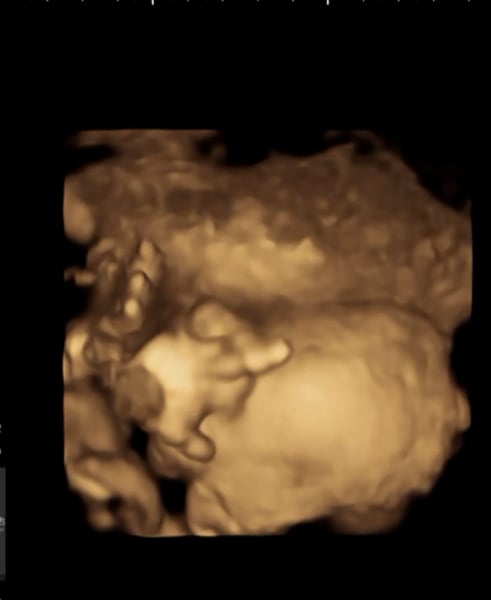

Had our 4D scan today and little lady was blowing us kisses 😚

29+2 for anybody who's interested (though measuring at 30+3 😳)

Got plenty of lovely pictures and she looked quite different to the sneak peek we had around 24-25 weeks.

Katlouise24 · 10/12/2022 14:26

We got our 4D scan too! We got a cheeky girl by the looks of her sticking her tongue out! Haha, all she did was yawn too🥹

botleybump · 10/12/2022 14:27

Aha! Adorable!

Oooh I love these 4D scans! Makes me so sad my little terror wasn't playing ball ☹️

botleybump · 10/12/2022 18:24

Aww! If it helps...our little lady got sick of all the attention and definitely gave us the finger towards the end 😂

Such gorgeous scans 🥰 we're going to book one in for after Christmas and take our mum's as a surprise, although both say the 3D scans are "creepy" haha

@TeddyBeans they had me up and walking 3 times to get baby girl to move...wasn't holding up hope until I sneezed and it woke her right up haha. I was there for 3 hours total!

These are the only pictures I got 😕 a skull and a third of her face